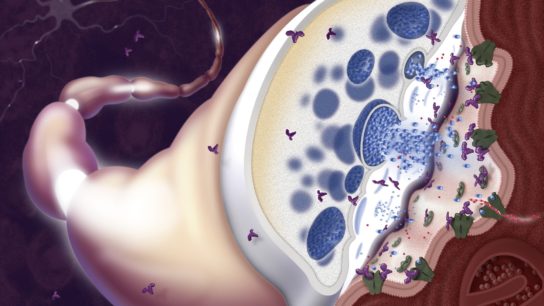

Research has revealed that the SARS-CoV-2 viral infection may have neurological manifestations, with critical implications for clinical practice.

Accumulating evidence suggests that COVID-19 can lead to neurological complications.

While neurological and psychiatric sequelae of COVID-19 have been reported, more data are needed to adequately assess the effects of COVID-19 on brain health.